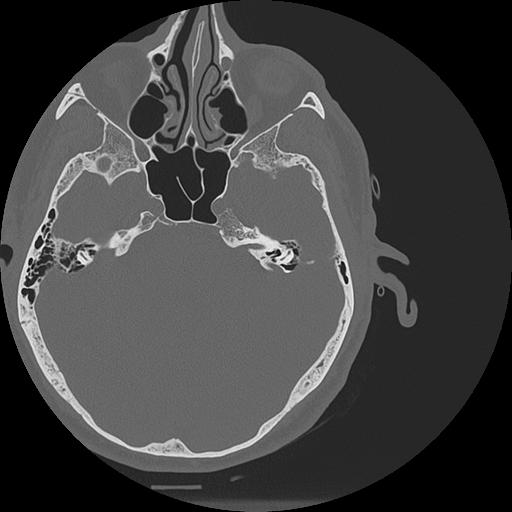

7 HUESO,,Vol,0.5,HUESO,,